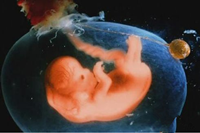

胎兒五個月時性器官已經(jīng)發(fā)育完善,你有沒有好奇懷孕五個月男胎兒長什么樣呢?如果你對此感興趣,不如一起來看看懷孕五個月男胎兒圖長啥樣...

懷孕六個月男胎兒圖什么樣?相信這是所有孕媽都感興趣的話題吧。懷孕進(jìn)入六個月后,此時孕媽會越來越感覺得到胎兒的存在,大多數(shù)的孕媽這個時候已經(jīng)擺脫了妊娠的各種不良癥狀...